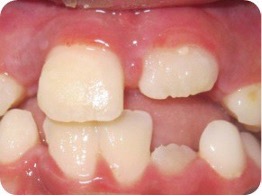

Se presenta el caso de un paciente de sexo femenino, de 8 años de edad. La paciente acudió acompañada con su padre al servicio de endodoncia del Instituto Nacional de Salud del Niño en Lima- Perú, con antecedentes de traumatismo dental, en sector antero superior y con dolor espontáneo. Al examen clínico intraoral, se evaluó que el diente 11 presentaba una ligera movilidad dental y al examen radiográfico se observó diente 11 no vital, ligero ensanchamiento del ligamento periodontal y desarrollo radicular en estadio 8 de Nolla (Figura 1 y 2). Se evaluó el caso y se realizó la explicación de las ventajas y desventajas del tratamiento de revascularización pulpar al padre de familia y se procedió a la firma del consentimiento informado para el tratamiento.

Figura 1: Pza. 11 con antecedentes de traumatismo alveolo dentario.